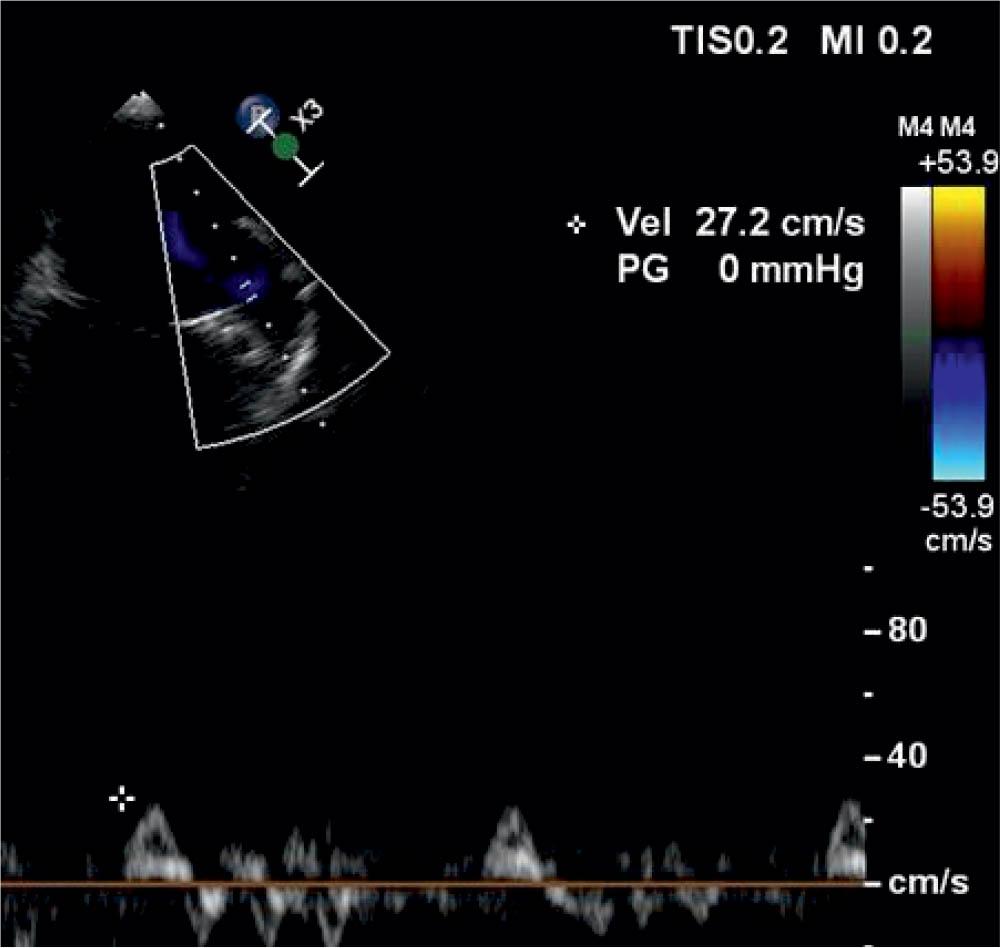

LAA contractile function can be characterized by the LAA flow velocity which can be measured with pulse-wave Doppler on TEE (Figure 2).

The measurement of LAA flow velocity with pulse wave Doppler. This image represents a decreased LAA flow velocity (27.2 cm/s) in a patient with AF. Courtesy Heart and Vascular Center of Semmelweis University, Budapest, Hungary.